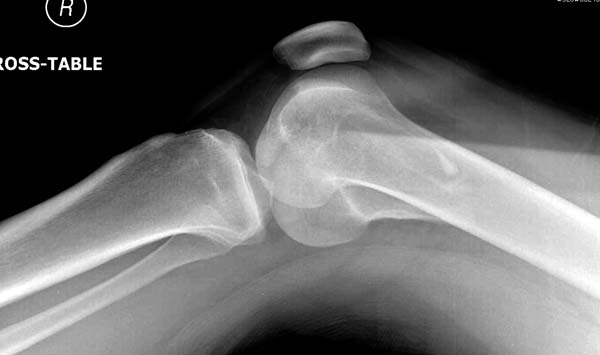

“Перелом наружного мыщелка правого бедра во фрональной плоскости был не замечен”

Диагностическая ошибка происходит, когда игнорируется правила обследования внутрисуставных переломов. Вместо полного обследования, включая КТ, ограничиваются рентгенограммой, и то в одной проекции!

Спасибо большое за советы! Добавляю некоторые КТ снимки. Перелом коллеги не диагностировали, видимо, расценив костную травму как повреждение задне-латерального комплекса коленного сустава. Отпишусь по результату выполненной операции.